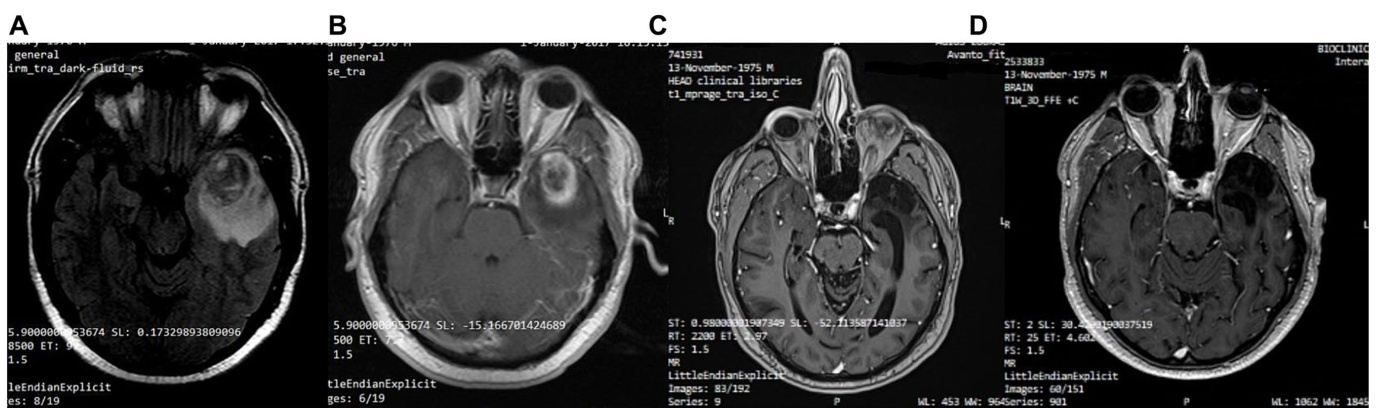

A 41-year-old man was diagnosed with GBM of the left temporal lobe on December 2016 following a brain MRI (Figure 3). The presenting symptom was persistent headache and gradual wordfinding difficulty (anomic aphasia). He underwent surgical resection in January 2017, followed by 30 sessions of radiotherapy $(60\mathrm{Gy})$ along with chemotherapy (temozolomide). His to pathological examination was typical of GBM with IDH1-negative/MGMT-nonmethylated (Figure 4). On March 2017, the patient was started on a calorie restricted 1.4:1 ketogenic diet as adjunctive therapy (Table 3). Blood ketones and glucose levels were self-monitored daily. The patient achieved adequate ketosis during the first week of instituting the ketogenic diet and maintained high ketone levels $\left(3{-}4\mathrm{mmol/L}\right)$ and adequate blood glucose levels $\mathrm{(60-90~mg/dL)}$ ) throughout the observational period. The ketogenic diet was well tolerated, with only mild gastrointestinal side effects (constipation). In addition, he received temozolomide, initially dosed at $100\mathrm{mg/m^{2}/d a y}$ every other week. After 1 month, his dose increased to $200\mathrm{mg/m^{2}/d a y}$ on the same schedule, without toxicities. Temozolomide maintenance treatment lasted for 2 years. Serial MRI brain imaging was obtained every 4 months. His follow-up brain MRI 79 months after diagnosis shows no evidence of tumor recurrence (Figure 3). The patient reports a residual mild anomia and is currently working as a teacher. His most recent ECOG grade is 0.

一名41岁男性患者于2016年12月经脑部MRI (图3) 确诊为左颞叶胶质母细胞瘤 (GBM) 。主要症状为持续性头痛和渐进性命名障碍 (命名性失语) 。2017年1月接受手术切除,随后进行30次放疗 $(60\mathrm{Gy})$ 联合替莫唑胺化疗。病理检查显示典型IDH1阴性/MGMT非甲基化的GBM特征 (图4) 。2017年3月起,患者开始采用1.4:1热量限制生酮饮食作为辅助治疗 (表3) ,每日自行监测血酮和血糖水平。实施生酮饮食首周即达到理想酮症状态,并在整个观察期间维持较高酮体水平 $\left(3{-}4\mathrm{mmol/L}\right)$ 和正常血糖范围 $\mathrm{(60-90~mg/dL)}$ 。该饮食方案耐受性良好,仅出现轻微胃肠道副作用 (便秘) 。同步接受替莫唑胺治疗,初始剂量为隔周 $100\mathrm{mg/m^{2}/d a y}$ ,1个月后按相同方案增至 $200\mathrm{mg/m^{2}/d a y}$ ,未出现毒性反应。替莫唑胺维持治疗持续2年,每4个月进行系列脑部MRI复查。确诊79个月后的随访MRI显示无肿瘤复发迹象 (图3) 。患者目前遗留轻度命名障碍,从事教师职业,最新ECOG评分为0级。

FIGURE 3 Patient 1: (A) Pre-operative brain MRI (T2/FLAIR) (B) Pre-operative brain MRI (T1 with contrast) (C) 38-month follow-up brain MRI (T1 with contrast) (D) 80-month follow-up brain MRI (T1 with contrast).

图 3: 患者1: (A) 术前脑部MRI (T2/FLAIR) (B) 术前脑部MRI (T1增强) (C) 38个月随访脑部MRI (T1增强) (D) 80个月随访脑部MRI (T1增强)。